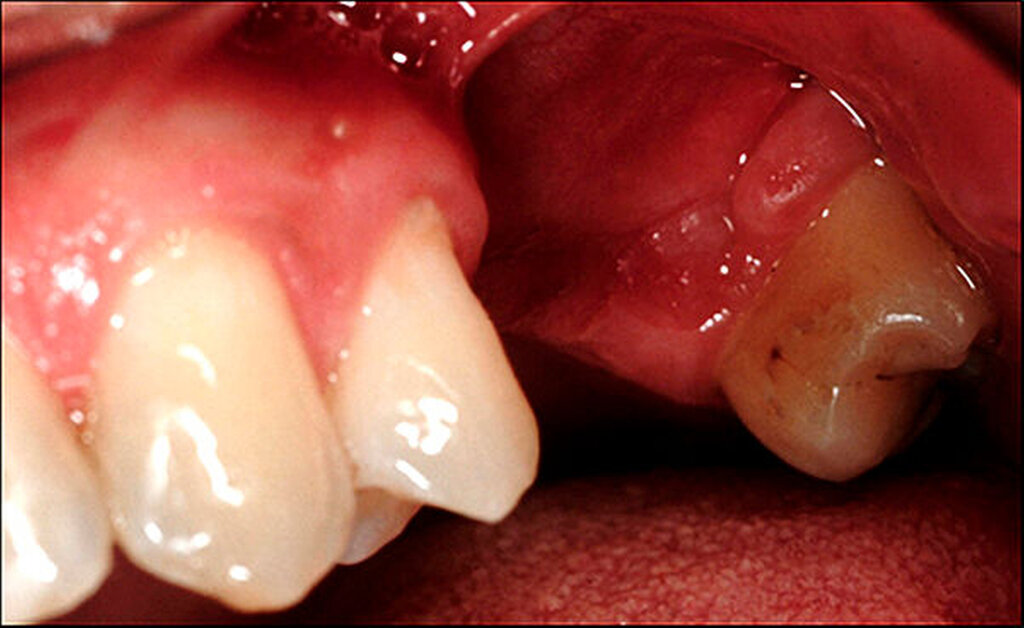

In der Zahnmedizin steht die oben beschriebene Homöopathie zwar nicht im Fokus, deren Weltbild kann aber als eine Art Einstieg in die alternativmedizinische Szene dienen. Sie kann dazu beitragen, sich weiteren alternativmedizinischen Modellen zu nähern, die ihrerseits für die Mundgesundheit gefährlich werden können, wenn sie beispielsweise zu drastischen invasiven Eingriffen mit irreversiblen Schäden motivieren. So gibt es Behandler, die auf der Grundlage sogenannter bioenergetischer Testmethoden (beispielsweise Muskeltests mit „Applied Kinesiology“) invasive Eingriffe wie Entfernungen intakter zahnärztlicher Versorgungen oder Zahnextraktionen (zuweilen sogar Serienextraktionen) vornehmen, unabhängig davon, ob die Versorgungen beziehungsweise Zähne nach aktuellem wissenschaftlichem Erkenntnisstand erhaltungswürdig sind oder nicht. Zahnärzte fräsen im Anschluss an Zahnextraktionen die Kieferknochen zur Beseitigung von vermeintlichen „Störfeldern“ aus und richten dabei erhebliche Schäden an (Abbildung 1).